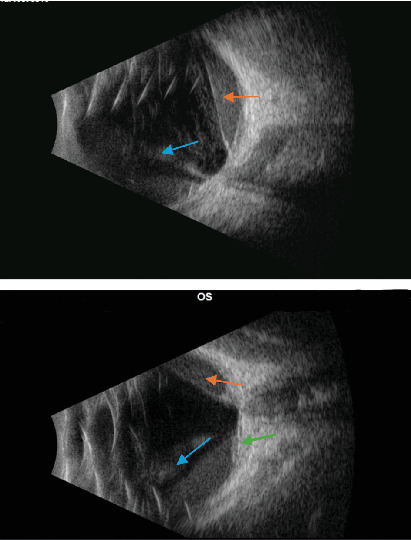

目的:本研究旨在描述一个免疫功能低下患者合并巨细胞病毒性视网膜炎和玻璃体出血的病例。观察:一名38岁男性,已知感染艾滋病毒,来到我们的急诊科,抱怨他的左眼视力下降。检查发现玻璃体出血和视网膜前出血,认为是由巨细胞病毒性视网膜炎引起的。初步治疗后病情恶化,考虑诊断为巨细胞病毒性视网膜炎合并血管炎,并给予相应治疗。结论:免疫功能低下患者的玻璃体出血不应仅仅归因于缺血性血管炎,应仔细检查并发感染性视网膜炎的可能性,以免延误治疗。

Purpose: This study is aimed at describing a case of combined CMV retinitis and vitreous hemorrhage in an immunocompromised patient. Observations: A 38-year-old male who is known to have HIV presented to our emergency department complaining of decreasing vision in his left eye. Vitreous hemorrhage and preretinal hemorrhage were observed upon examination and were thought to be caused by CMV retinitis. After initial treatment and worsening condition upon follow-up, a diagnosis of combined CMV retinitis and vasculitis was considered and was treated accordingly. Conclusions: The presence of vitreous hemorrhage in immunocompromised patients should not be attributed to just an ischemic vasculitis alone, and the possibility of concurrent infectious retinitis should be looked for carefully to avoid delay in treatment.